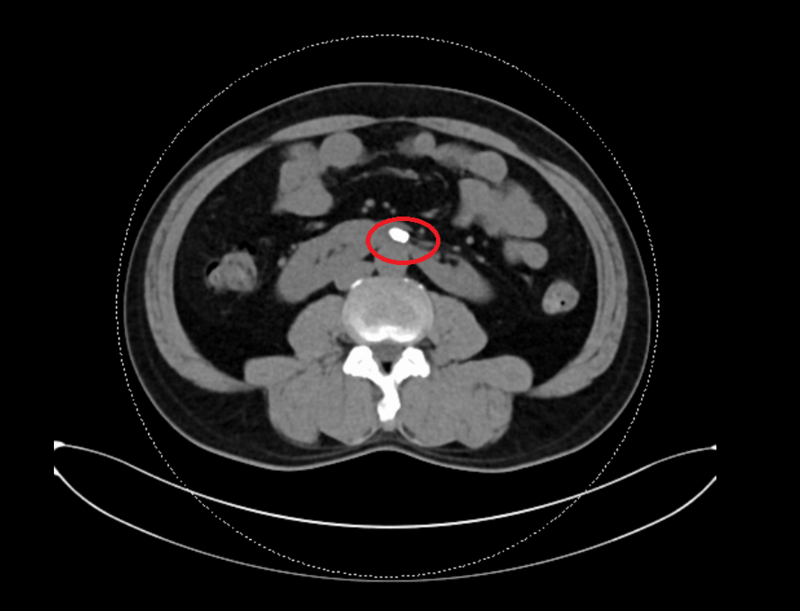

张先生术前左右肾连接狭窄处结石

检查结果出来后,让医生有些头大,因为张先生的结石正好卡在左右肾连接的“咽喉要道”,这让手术难度直接升级!